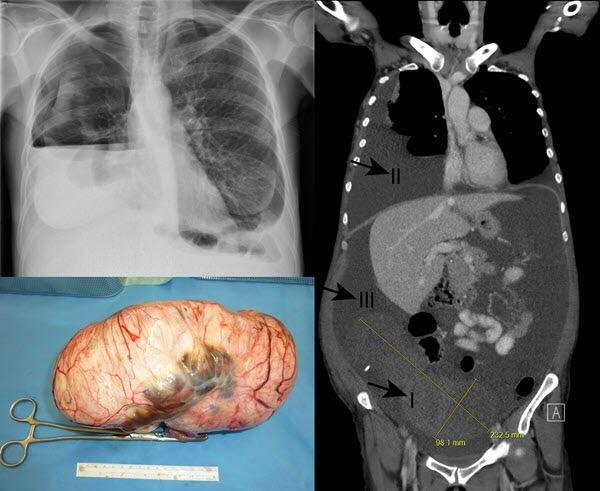

মেগস সিন্ড্রোম পদার্থের তরল পদার্থ (এসসিআইটিইএস) বা ফুসফুসের এবং বুকের প্রাচীর (পিরিয়টিক ফুসফুসের) এর মধ্যে একটি ডিম্বস্ফিয়ারের FIBRRO বা অন্য টিউমারের সাথে সংযুক্ত স্থান। শর্তটি হচ্ছে বোতুলুম টক্সিনের সাথে চিকিত্সা করা হচ্ছে। (জো ভিনসেন্ট মেগস, 18২9-1963, আমেরিকান গাইনিকোলজিস্ট)।

মেগস সিনড্রোম - হাইড্রফেরিটিনিয়াম এবং হাইড্রোথোরাক্সের সাথে যুক্ত ডিম্বাশয়ের ফাইব্রোমিওমা। সমার্থক শব্দ (গুলি):IMG_4849.JPG